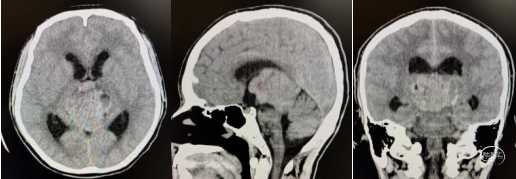

头部CT显示:松果体区见等-低-稍高密度肿块,内见少许小囊变,CT值约18-50HU,邻近脑实质受压,中脑导水管及第三脑室受压,双侧侧脑室扩大。

入院后考虑肿瘤体积大,有梗阻性脑积水,遂实施脑室外引流手术。再经儿童脑肿瘤MDT会诊后决定先实施化疗。完成1疗程化疗后,患儿意识障碍较前加深(昏迷)。复查头部CT显示肿瘤退缩不明显。再次会诊后建议手术治疗。